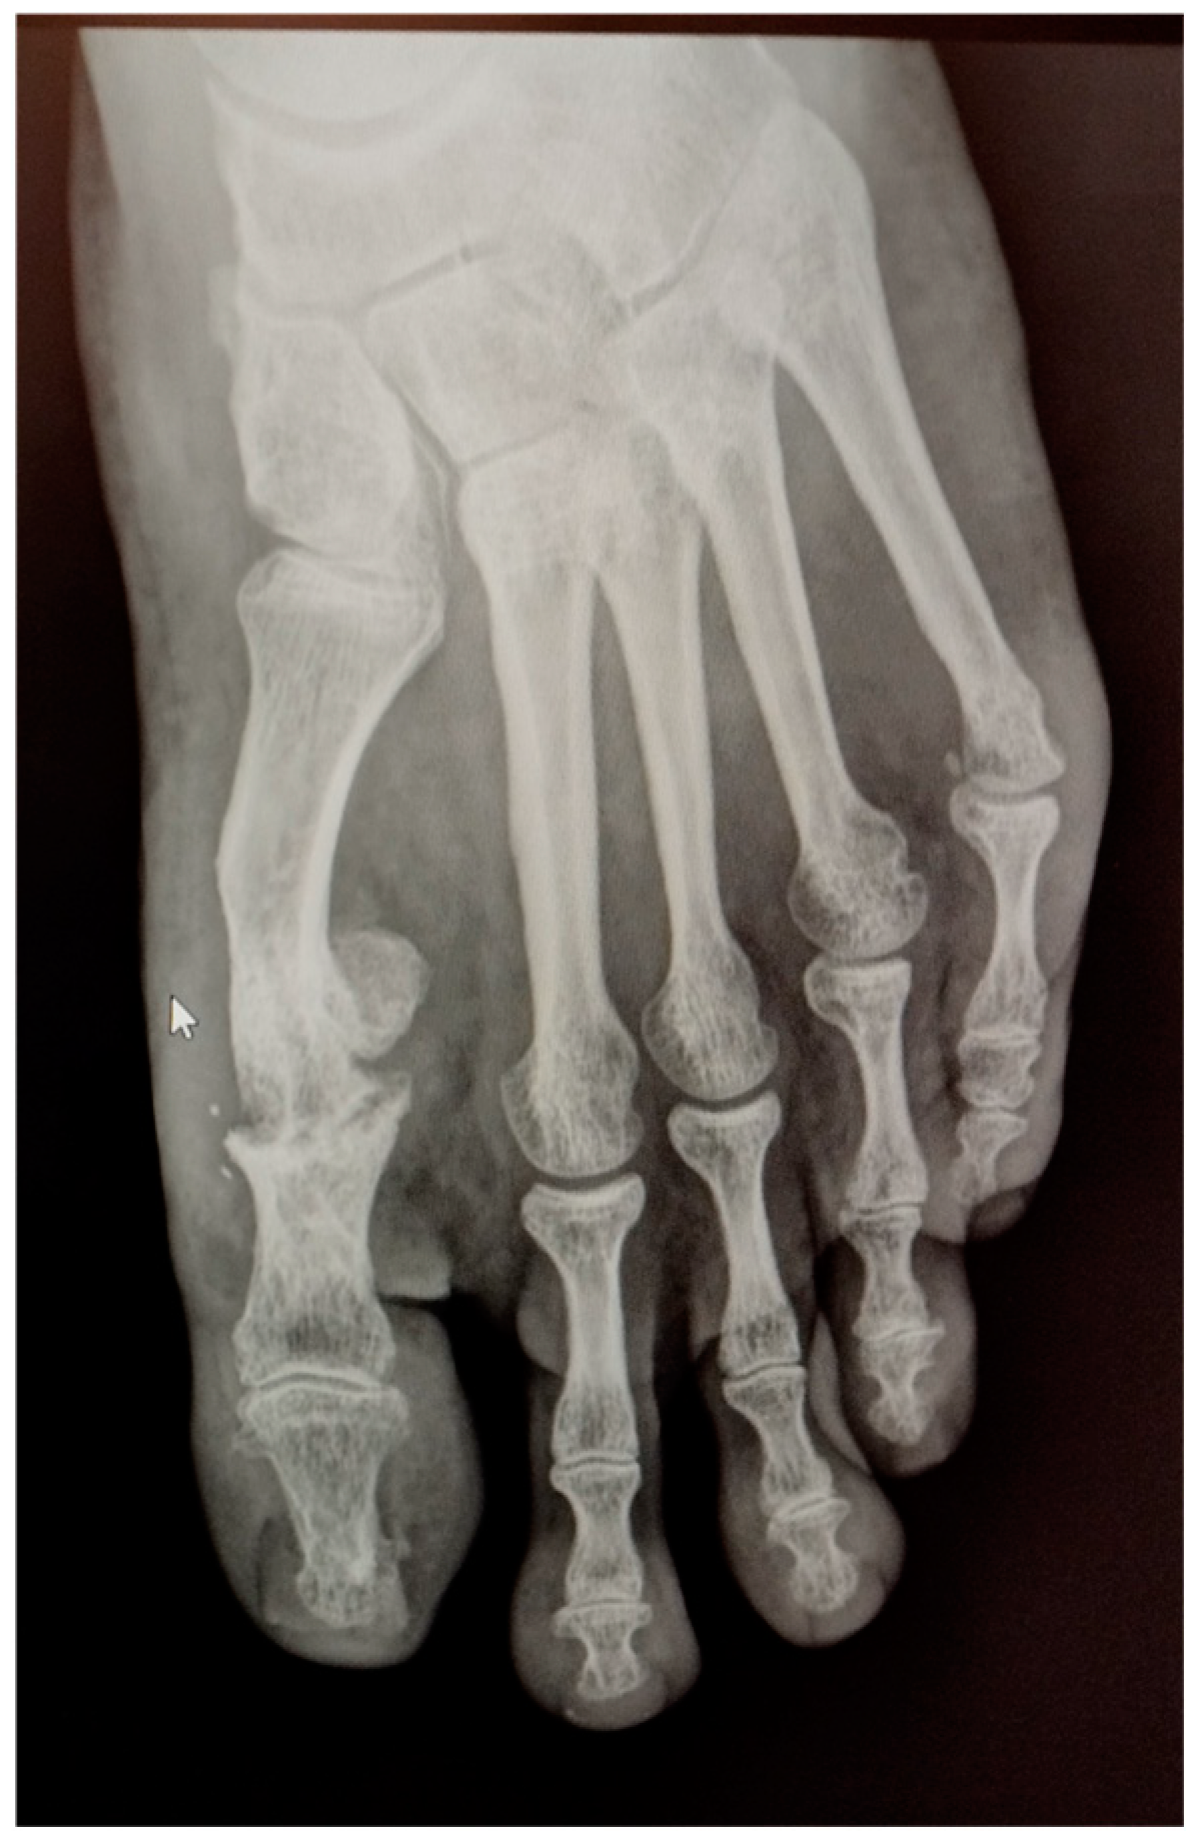

Radiographic examination after one year following the second surgery showed signs of severe joint destruction compatible with MPJ resection arthroplasty with significant shortening of the first toe (Figure 5). The patient was treated conservatively with orthopaedic insoles.

Figure 5.

Postoperative radiography one year after the second procedure. Signs of severe joint destruction compatible with resection arthroplasty can be observed.